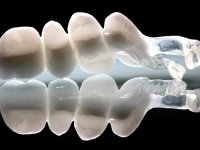

Paciente do sexo feminino, com 69 anos, não fumadora. Apresenta uma prótese combinada no maxilar superior. A porção fixa corresponde a uma ponte metalo-cerâmica de 4 elementos com os dentes 1.3/1.1 e 2.1 como pilares e o dente 1.2 como pôntico. A porção amovível corresponde a uma prótese esquelética de 5 elementos. A retenção da prótese esquelética é feita por um gancho no dente 1.4 e um “attachment tipo t” colocado no dente 2.1.

O estudo imagiológico para a colocação dos implantes, começou com a realização em laboratório de uma guia com dentes em sulfato de bário. Esta guia foi colocada em boca conjuntamente com marcas de referência coladas aos dentes, também em sulfato de bário. A guia foi estabilizada com cera mole. A TAC foi realizada com estas referências colocadas em boca. Após a realização da TAC foi feita uma impressão de arrasto em silicone. Esta impressão foi vazada a gesso em laboratório e posteriormente digitalizada. A digitalização do modelo com as referências foi sobreposta á imagem da TAC, permitindo uma planificação apurada na colocação dos implantes. Na planificação foi decidido colocar 2 implantes no local dos dentes 2.3 e 2.4 evitando-se a zona do 2.2 com pouco osso e o seio maxilar. Este estudo deu origem a uma guia cirúrgica que orientou a colocação dos implantes. Durante o período de osteo-integração a paciente utilizou a prótese removível rebasada com acondicionador de tecidos. A guia cirúrgica mostrou-se também útil na exposição dos implantes mostrando a sua localização precisa e orientando a incisão. A impressão definitiva foi realizada utilizando a técnica de moldeira aberta após eliminação do attachment. No laboratório foi confeccionada uma ponte metalo-cerâmica de 3 elementos com o elemento 2.2 em suspensão. A ponte após verificação e aprovação foi cimentada. A reabilitação apesar de pouco extensa (sem o elemento 2.6) mostrou-se capaz estetica e funcionalmente.